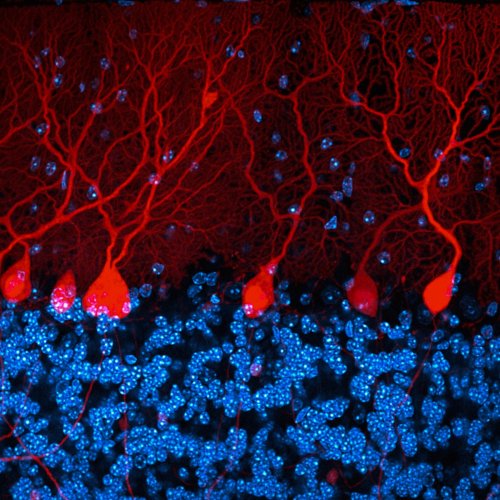

Мозговое вещество трансгенной мыши в 3D